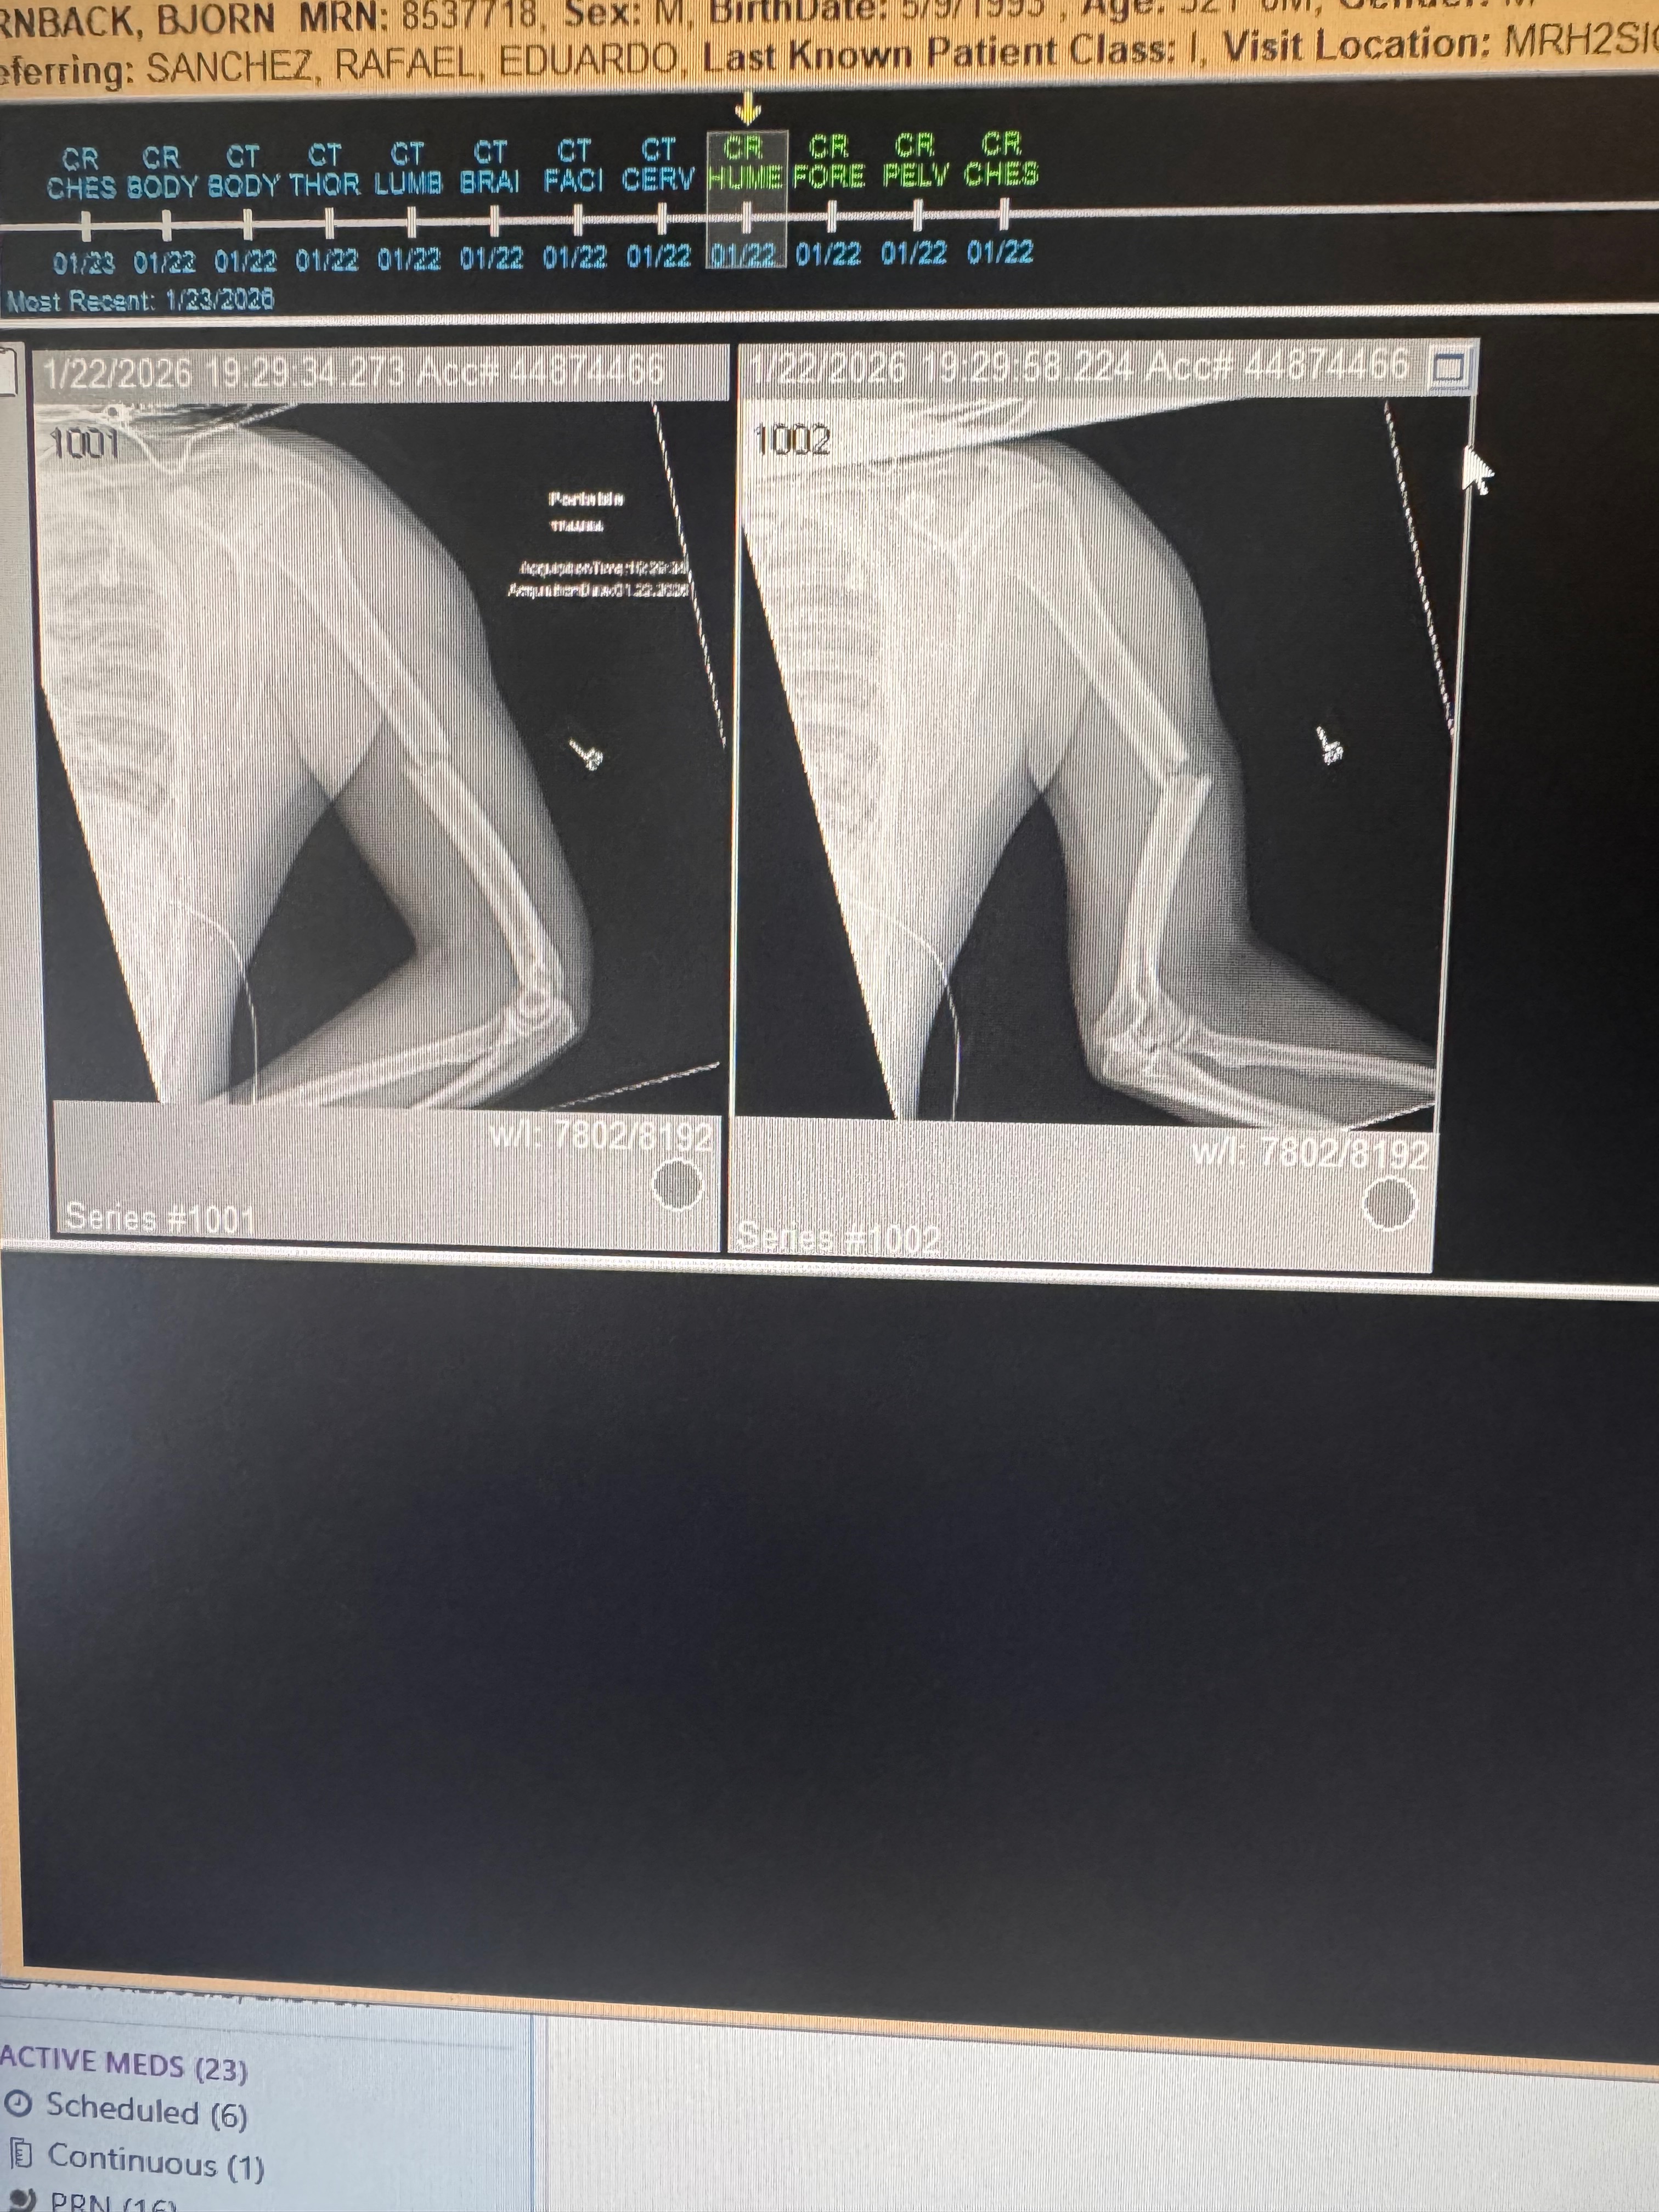

My name is Bjorn, and I’m reaching out because I recently experienced a life-changing motorcycle accident. In an instant, my world was turned upside down when I snapped my arm and broke my knee. The pain and shock were overwhelming, and I’m now facing a long and difficult recovery.